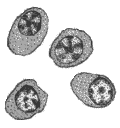

Согласно Международной гистологической и цитологической классификации опухолевых заболеваний кроветворной и лимфоидной тканей, в основу которой положен клеточный состав новообразований и характер распространения, опухоли системы крови, или гемобластозы, делят на две группы: лейкозы (лейкемии) – системные опухолевые заболевания кроветворной ткани; лимфомы – регионарные опухолевые заболевания кроветворной и/или лимфоидной ткани. Такое деление является в значительной степени условным, поскольку ограниченный опухолевый рост и диффузная опухолевая инфильтрация могут иметь место одновременно или последовательно у одного больного. Актуальность проблемы Лейкемии и лимфомы, включая лимфому Ходжкина, составляют приблизительно 8% от всех злокачественных новообразований и все вместе входят в число 6 самых частых видов злокачественных опухолей. В США каждый год лейкемиями заболевает около 25000 человек, из них умирает 15000-20000. Уровень смертности в последнем десятилетии резко снизился в результате повышения эффективности терапии. Острые лейкемии составляют около 50-60% от всех лейкемий, причем острая миелобластная лейкемия встречается несколько чаще, чем острая лимфобластная лейкемия. Хронические лейкемии составляют около 40-50% от всех лейкемий, причем хроническая лимфоцитарная лейкемия встречается несколько чаще, чем хроническая миелоцитарная лейкемия (рис. 1). Рис. 1. Заболеваемость различными видами лейкемий в зависимости от возраста ОЛЛ – острая лимфобластная лейкемия; ХЛЛ – хроническая лимфоцитарная лейкемия; ОМЛ – острая миелобластная лейкемия; ХМЛ – хроническая миелоцитарная лейкемия. В последние годы получила распространение в большинстве стран классификация франко-американо-британской группы гематологов (FAB-система, табл. 1). Согласно этой классификации выделяют три варианта острого лимфобластного лейкоза (L1, L2, L3) в зависимости от размеров бластов, структуры ядра и цитоплазмы, а также по иммунологическим (иммуноморфологическим) или генетическим признакам (см. табл. 2, 5). Острая миелобластная лейкемия также классифицируется по FAB-системе в зависимости от “зрелости” и направленности дифференцировки лейкозных клеток. Она включает типы М1, М2, М3, М4, а также моноцитарную лейкемию (М5), эритролейкемию (М6) и мегакариоцитарную лейкемию (М7), которые обычно рассматривают отдельно. Таблица 1 Франко-американо-британская классификация острых лейкемий Острая лимфобластная лейкемия (ОЛЛ) L1 «Гомогенные» лимфобласты среднего размера; иммунологически немаркируемые, но охватывающие несколько типов, включая простую ОЛЛ и пре-В ОЛЛ; встречается у детей; имеет самый хороший прогноз. L2 Гетерогенные бластные клетки; также смешанная группа, некоторые немаркируемые, Т-клеточные; наблюдается обычно у взрослых и имеет плохой прогноз. L3 Гомогенные базофильные бластные клетки (типа клеток при лимфоме Беркитта), состоит из В-клеток и имеет плохой прогноз. Острая миелобластная лейкемия (ОМЛ) M1 Состоит только из миелобластов без созревания M2 Миелобласты с признаками созревания M3 Острая промиелобластная лейкемия; промиелобласты имеют множество темных азурофильных цитоплазматических гранул. M4 Острая миеломонобластная лейкемия, развивающаяся из общих клеток-предшественников моноцитов и гранулоцитов. M5 Острая монобластная лейкемия M6 Эритролейкемия (синдром Ди Гуглиельмо; доминируют эритробласты при присутствии миелобластов. M7 Мегакариобластная лейкемия Монобластная лейкемия подразделяется на два типа лейкемий: острую монобластную (тип Шиллинга) и острую миеломонобластную (тип Нигели). Не существует хронических форм лейкемий данного типа. Острая моноцитарная (монобластная) лейкемия характеризуется пролиферацией монобластов. Они могут быть отдифференцированы от других бластов только при использовании цитохимических маркеров (табл. 2). Острая миеломоноцитарная лейкемия характеризуется наличием бластов, которые имеют признаки миелобластов и монобластов как морфологически, так и цитохимически. Таблица 2 Цитохимическая идентификация острых лейкемий